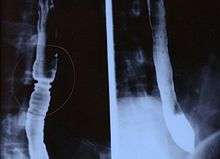

Radiologically, the term "ringed esophagus" has been used for the appearance of eosinophilic esophagitis on barium swallow studies to contrast with the appearance of transient transverse folds sometimes seen with esophageal reflux (termed "feline esophagus").[7]